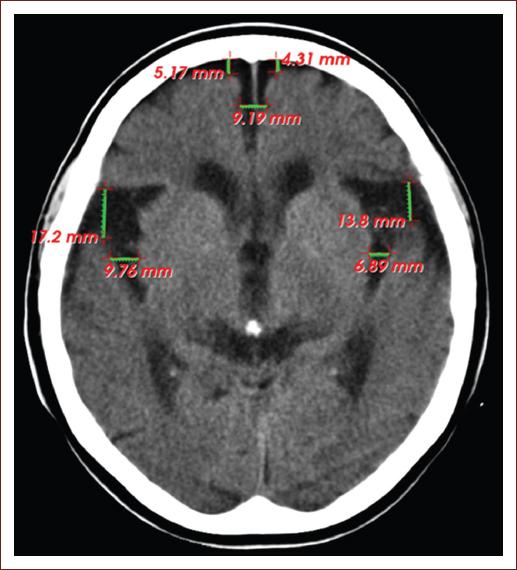

Special attention in radiological practice is given to the frontal horns of the lateral ventricles, at the level of the Monro hole, the amplitude of these in people under 40 years is < 12 mm, and in those over 40 years < 15 mm9. Dilation of the grooves (Fig. 1) and cisterns (Fig. 2) is part of the normal aging process, normal values are considered 4 mm of brain skull distance and 6 mm of interhemispheric width10. To understand structural and functional changes of the brain, research in the field of neuroscience in the 21st century has been an excellent contribution but is still insufficient4.

Figure 1 Computed tomography image of the simple skull of a 75-year-old patient, without neurologic focalization signs, showing signs of cerebral atrophy with deepening of the grooves at the frontal level (5.17 and 4.31 mm, respectively), of the anterior portion of the interhemispheric fissure (9.19 mm) and dilation of the grooves of Silvio (17.2 and 13.8 mm on both sides) and Rolando (9.76 and 6.89 mm on both sides) (source: Imaging Department, Juan Bruno Zayas Alfonso Hospital).